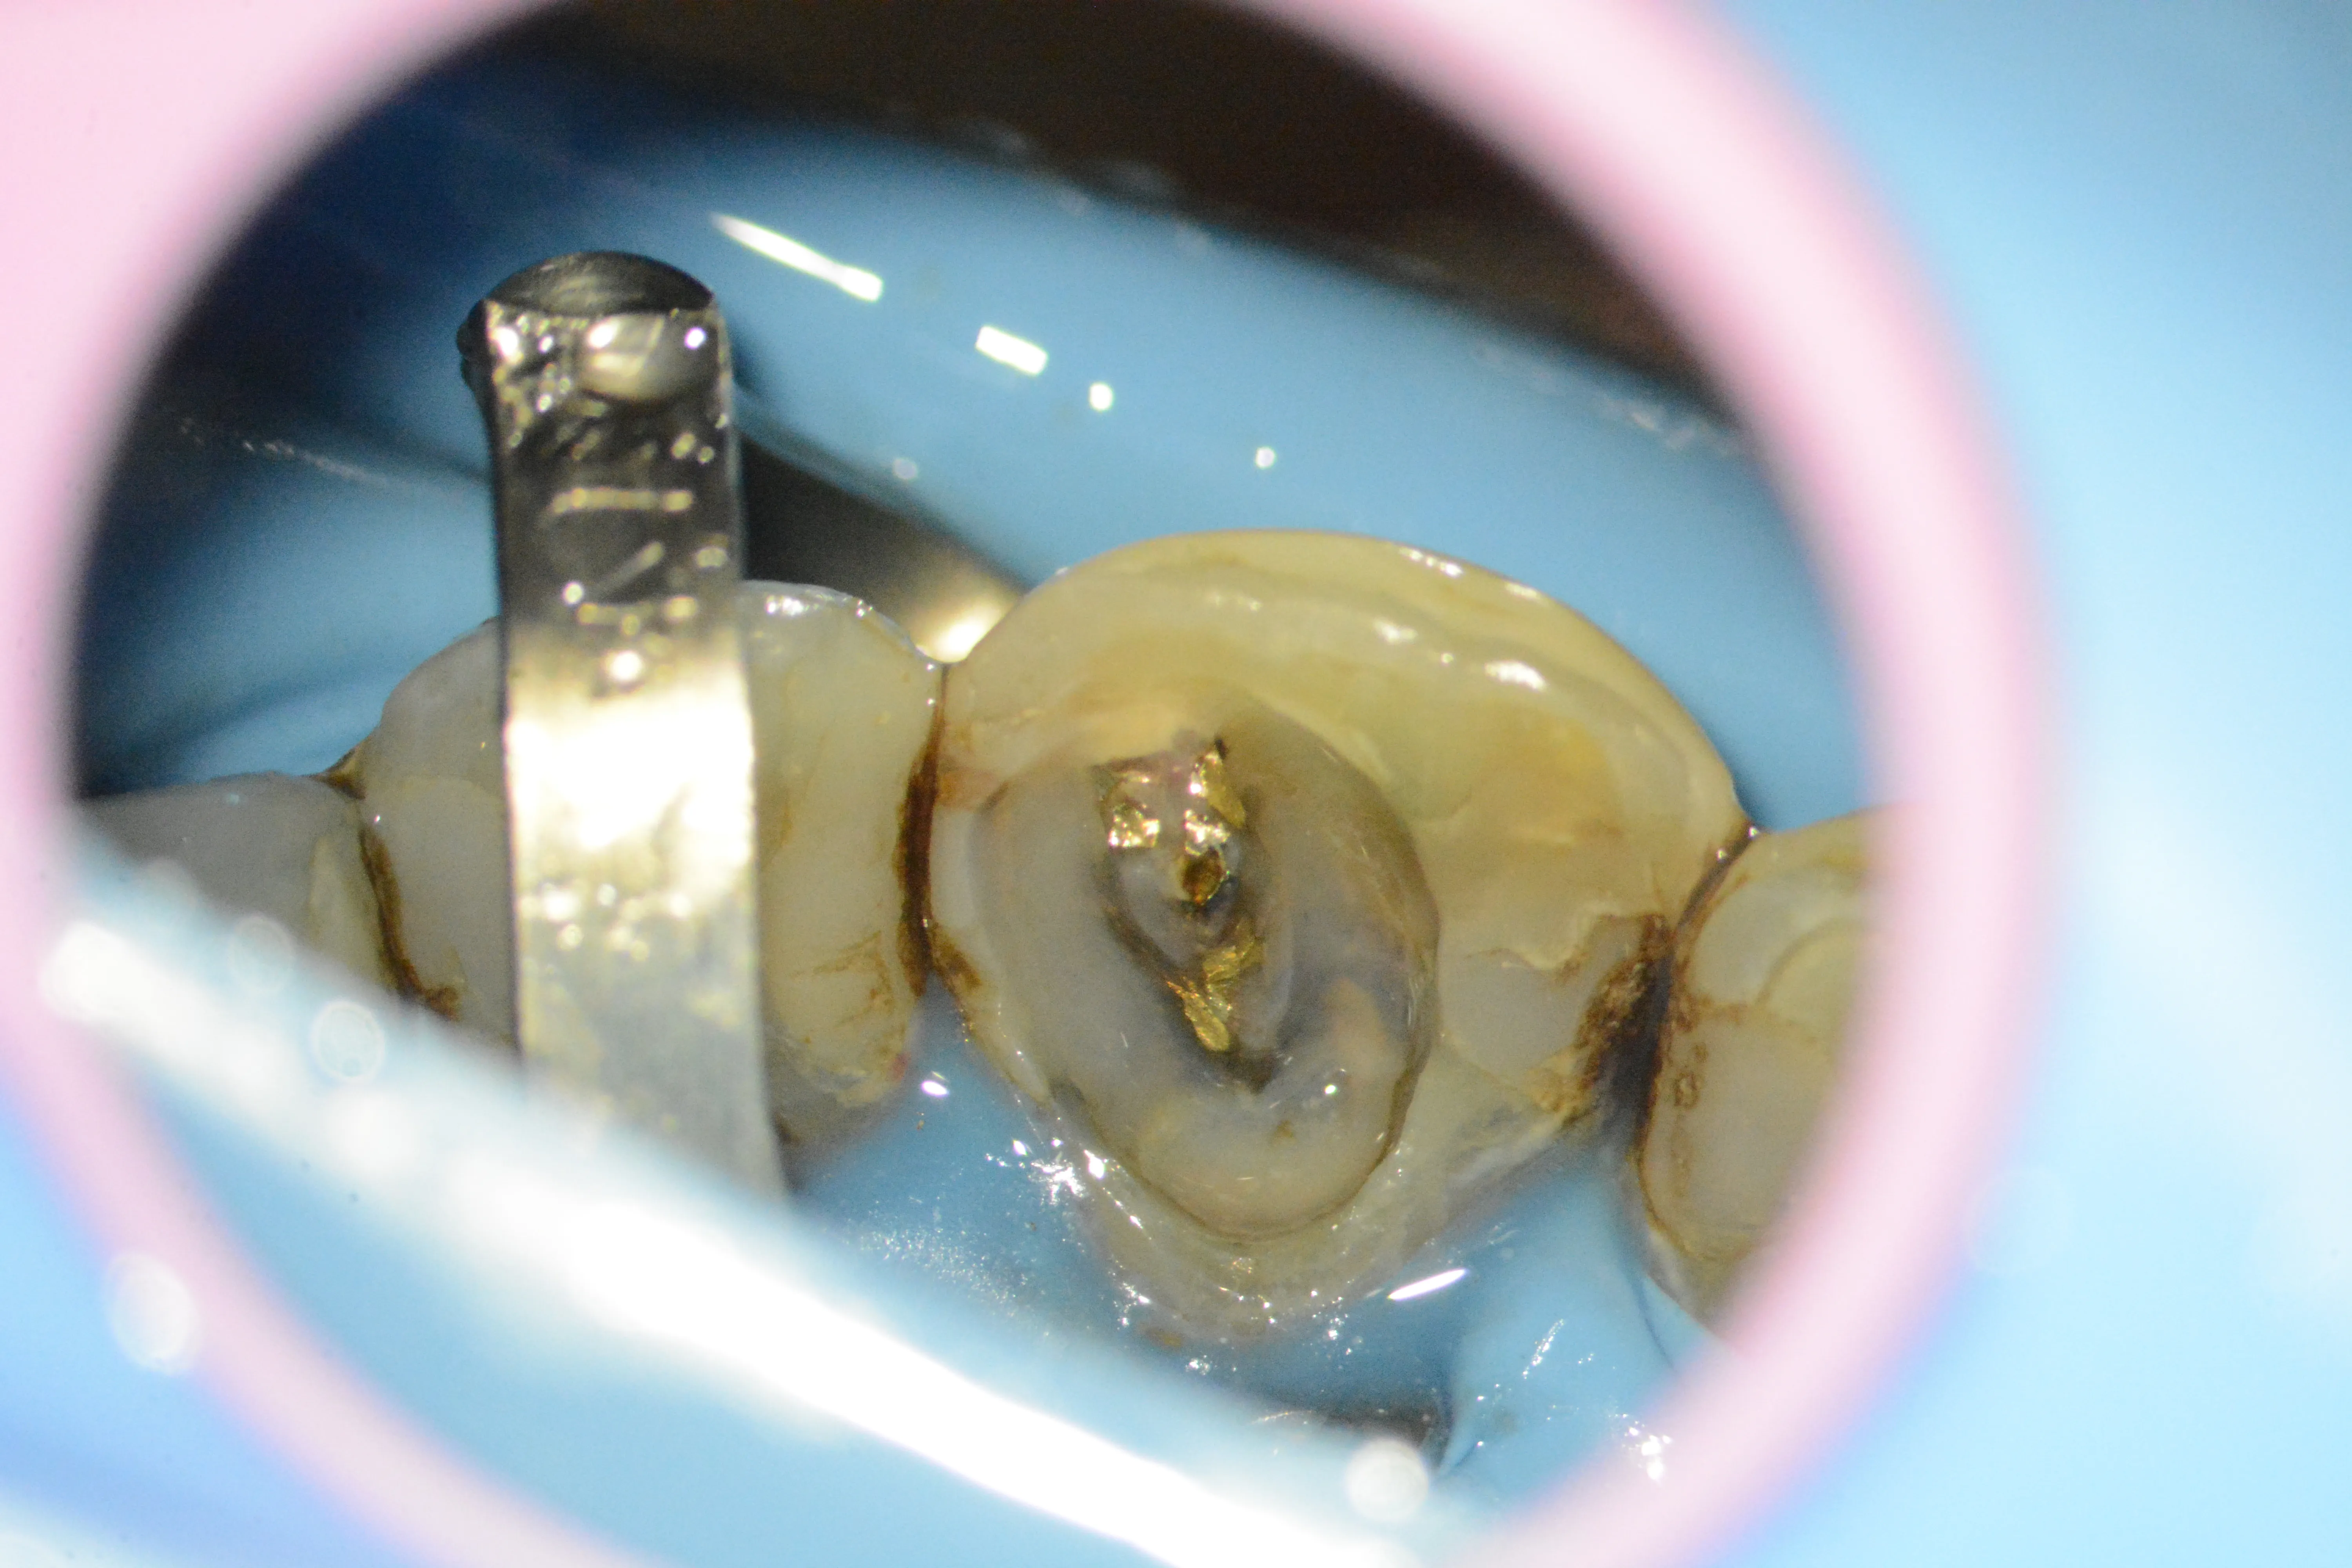

17 – Aplicarea matricei și a ic-urilor în vederea reconstrucției